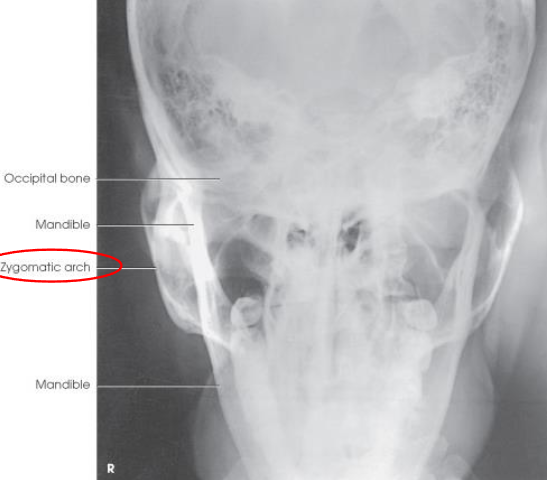

AP axial (Towne) skull

patient and part position:

supine or upright, seated

MSP centered to midline

MSP perpendicular

OML perpendicular to IR

IOML perpendicular if patient cannot flex neck enough

top border of IR level with vertex

IR centered at or near foramen magnum

respiration suspended

CR:

directed through foramen magnum

OML: 30 degrees cacudal

IOML: 37 degrees caudal

collimation:

1 inch beyond the skin line of the skull

AP axial (Towne) skull image criteria

no rotation:

equal distance from lateral border of skull to lateral margin of foramen magnum

symmetric petrous ridges

dorsum sellae and posterior clinoid process visible within foramen magnum

penetration of occipital bone without excessive density at parietals